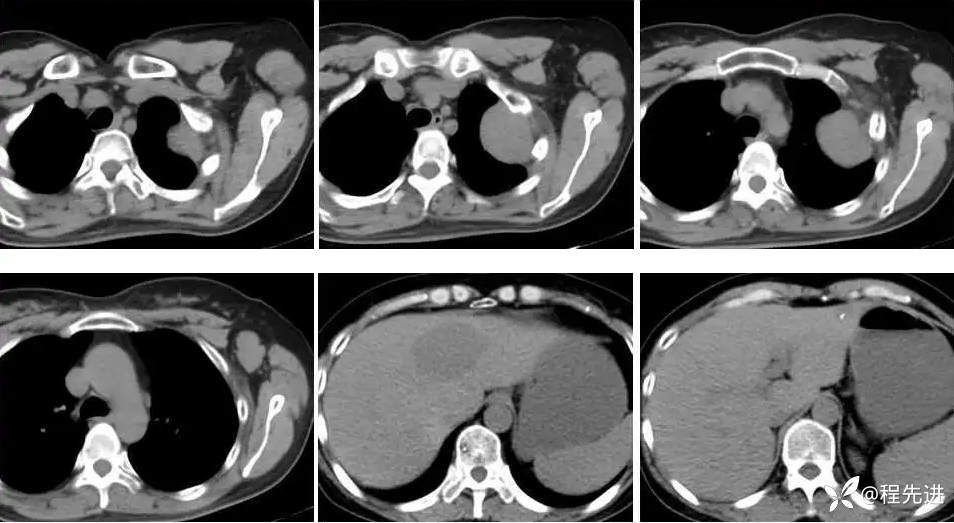

【主诉】:发现左胸部软组织肿块伴左侧腋窝淋巴结肿大1周

【现病史及既往史】:患者1周前因体检发现左肺上叶软组织肿块伴左侧腋窝淋巴结肿大。病程中患者无咳嗽咳痰,无胸闷胸痛,无发热、头痛、头昏、腹胀等不适精神及食纳尚可,二便正常